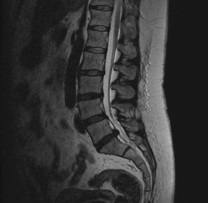

治療について

受診された際には問診、診察を行い、画像検査(レントゲン、MRI、CT)や採血検査を行い、診断を付け、治療方針を説明します。 上記のような保存治療を行っても取れない痛みや、手の使いにくさや歩行困難、排尿排便障害などが出現し症状が進行性の場合は手術加療が必要となります。

手術・検査

なるべく低侵襲で体の負担が少ない手術を行います。低侵襲な脊椎手術には、手術による傷が小さい、筋肉の損傷が少ない、出血量が少ない、時間が短い、術後の痛みが少ない、早期リハビリテーションが可能、早期退院が可能(10日程度)、早期社会復帰が可能、など多くの利点が挙げられます。

検査

当院では、術前の診断精度を高める目的で、神経根ブロック(左)やCTミエログラフィー(右)検査を行っています。検査後は、経過を確認する目的で1泊入院となりますが、翌日には退院が可能です。